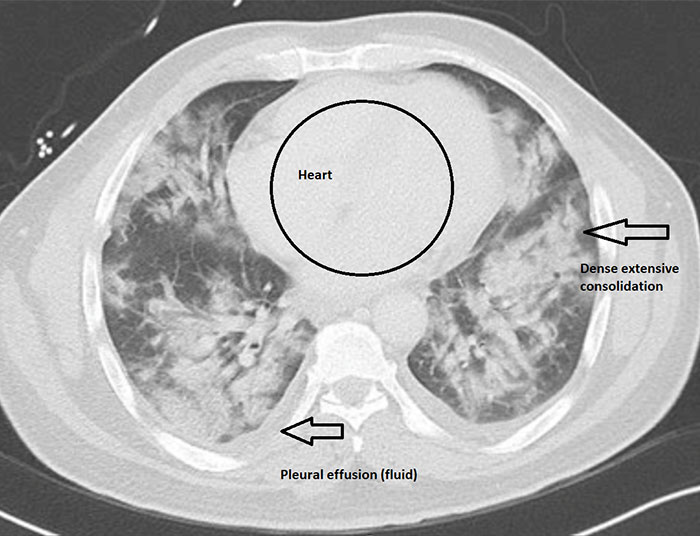

Imgur user and radiologist HeyYoMikey8 said the unknown future is the hardest part of the coronavirus pandemic. HeyYoMikey8 believes it is our own responsibility to educate ourselves so we can all do our part during these difficult times. So, to make it easier for us, the health professional shared what they’re seeing in cases of Covid-19 radiographically. The comprehensive commentary, as well as images used to help in the diagnosis and managing complications or evaluating the progression of the disease, should definitely broaden your understanding of what we’re all facing.

Interestingly, in the early days of the coronavirus outbreak, radiological imaging was not regarded as a way to confirm evidence for COVID-19 cases. Instead, authorities relied on a positive result of the PCR nucleic test. The supply of the PCR test kits, however, was limited and getting back the results took a long time. So, Chinese health authorities soon recognized these difficulties and changed the diagnostic strategy in their 5th edition of the Guidelines on Diagnosis and Treatment of COVID-19. As a result, radiological features of COVID-19 were included as one of the three determinant clinical manifestations to confirm a suspicious patient. The high efficiency, reliability, and accessibility of the radiological diagnostic technology have helped tremendously in identifying the disease. These processes were soon enhanced further by the introduction of artificial intelligence (AI) algorithms.

“Finally, all radiology is a business like any other, and we have canceled or deferred almost all elective imaging procedures to help stall the spread of infection and make room for a potential surge of COVID-19 cases,” the radiologist explained. “Therefore, our imaging volumes have dropped by upwards of 50% basically overnight, leaving us with a lack of work for our normal staffing (requiring forced vacations) and a large dip in revenue which jeopardizes our ability to pay the bills and keep our nonphysician employees employed and paid. I do think radiology has helped us at least in this early stage to identify many presumptive cases that were not being considered as COVID-19 at their presentation … It may be helpful for follow up evaluation for potential complications such as ARDS or pleural effusions. Also, there are patients with respiratory symptoms now concerning COVID-19 that have imaging findings/patterns more consistent with other etiology such as bacterial pneumonia or pulmonary embolism, therefore helping to rule out many cases and guiding other appropriate treatment.”